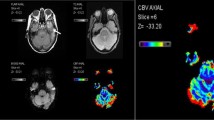

DSC MRI image-review protocol

ROIs covering the whole tumor and tumor hotspot were drawn on the slide representing the largest area of increased perfusion, and ROIs for the peritumoral region were drawn on the slide showing most T2 hyperintensity as correlated with the T2-weighted series and Fluid Attenuation Inversion Recovery (FLAIR) series. If perfusion data did not help to delineate the aforementioned tumor regions, T2, FLAIR and/or T1 post-contrast images were used as these are used in daily clinical practice to detect regions suspected for either early tumor progression or pseudoprogression. For each scan, a total of 6 ROIs were independently drawn by the three investigators who were all blinded to histopathological outcomes and clinical data at time of assessment. Consequently, a total of 18 ROIs per DSC-MR scan were obtained (Fig. 2).

Exemplary images of the different ROIs used for this study. On the left-handed side, the CBV maps are presented (A and C); on the right-handed side, the DSC-MRI source data are presented (B and D). ROI1 = Circular ROI covering the tumor hotspot; ROI2 = Circular ROI covering the peritumoral region; ROI3 = Circular ROI covering the whole tumor region; ROI4 = Polygonal ROI covering the tumor hotspot; ROI5 = Polygonal ROI covering the peritumoral region; ROI6 = Polygonal ROI covering the whole tumor region. DSC-MRI = dynamic susceptibility contrast magnetic resonance imaging; CBV = cerebral blood volume; ROI = Region of interest